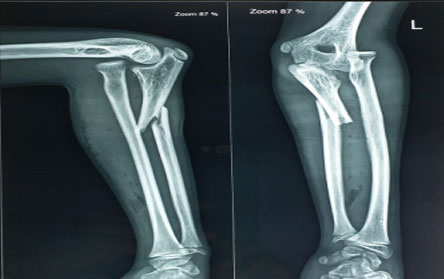

Trauma surgery:

Trauma surgery is a surgical specialty that utilizes both operative and non-operative management to treat traumatic injuries.

The Center of Orthopedics KUMAR ORTHO HOSPITAL ,Patna, offers the entire spectrum of modern orthopedic management, which is effective, patient - friendly & result oriented. In a nutshell, it is one stop treatment for all orthopedic ailments and fractures with emphasis on avoidance of complications, rapid mobilization, decreased period of confinement and an early return to normalcy.